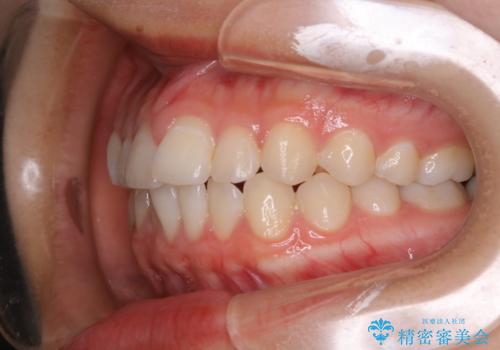

前歯のがたつきをインビザラインで治療

- 上下前歯のがたつきが気になるとの事で来院された患者様です。がたつきの程度が軽度であったため、インビザラインライトにて治療をおこないました。

がたつきの程度が軽度であったことと、インビザラインを正しく装着して頂けたことで短期間で治療終了することが出来ました。